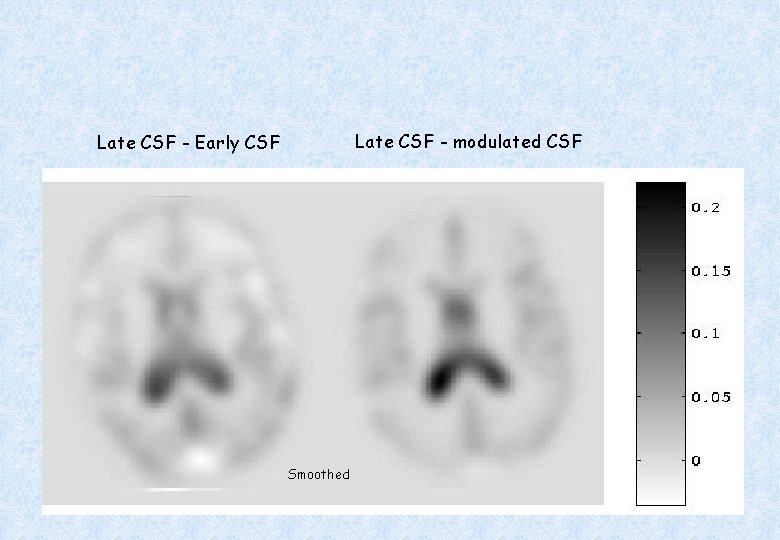

Late CSF - modulated CSF Late CSF - Early CSF Smoothed